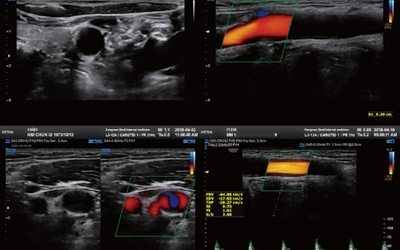

경동맥 초음파 검사는 목 부위에 위치한 경동맥의 상태를 실시간으로 확인할 수 있는 비침습적인 검사 방법입니다. 초음파를 이용하여 혈관 벽의 두께, 혈액의 흐름, 혈관 내 플라크(혈전)의 존재 여부 등을 파악할 수 있습니다. 마치 도로 위에 설치된 CCTV처럼, 혈관 속 상황을 안전하게 들여다보는 것이죠. 검사 과정은 간단하며, 통증이나 불편함이 거의 없어 누구나 부담 없이 받을 수 있습니다.

경동맥 초음파 검사는 다양한 경동맥 질환을 진단하는 데 유용한 도구입니다. 다음은 경동맥 초음파 검사를 통해 확인할 수 있는 주요 질환들입니다.